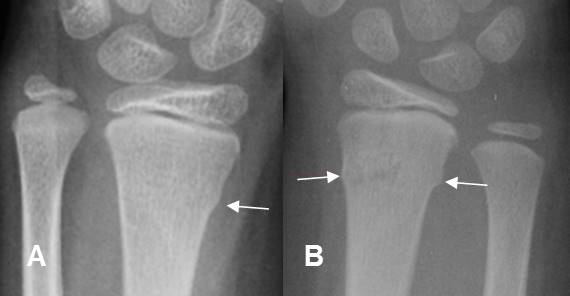

Fig 180. Fractura de Colles.

A: y B: Rx lateral de muñeca. Fractura de Colles, con desplazamiento posterior del fragmento distal del radio.